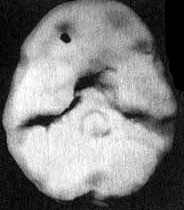

Вместе с Эндрю я отправился в отделение сканирования и, пока проводилось исследование, держал его за руку. Эндрю усадили в кресло, в вену ввели иглу, а через нее — малую дозу радиоизотопов. В это время Эндрю играл на ноутбуке в игру на концентрацию внимания. Через несколько минут иглу вынули, и он пошел в соседний кабинет, где делались снимки. Там его уложили на спину на специальный стол. В течение пятнадцати минут камера, медленно двигавшаяся по окружности вокруг головы Эндрю, производила съемку его мозга. Когда изображение было выведено на экран монитора, я подумал, что в ходе исследования была допущена какая-то ошибка. У Эндрю отсутствовала левая височная доля. Просмотрев все снимки, я убедился, что качество сканирования — хорошее. У него на самом деле не было левой височной доли. Что у него было? Киста? Опухоль? Инсульт? Рассматривая эти снимки на мониторе, я испытывал за него сильный страх. В то же время я чувствовал облегчение от того, что мы установили причину его агрессивности. В своих исследованиях и я, и мои коллеги установили связь между нарушениями в левой височной доле и агрессивностью. На следующий день на магнитно-резонансной томографии мы обнаружили у Эндрю на том месте, где обычно находится левая височная доля, кисту (мешок, заполненный жидкостью), размером с мячик для гольфа. Я знал, что эту кисту надо убрать. Однако поиск специалиста, который серьезно отнесся бы к нашим выводам, оказался трудным.

Отсутствие активности в левой височной доле у Эндрю

Трехмерное изображение нижней поверхности мозга

Иллюстрация к книге — Измените свой мозг - изменится и жизнь! [i_003.jpg]

Нормальный мозг

Иллюстрация к книге — Измените свой мозг - изменится и жизнь! [i_004.jpg]

Мозг Эндрю — левой височной доли не видно